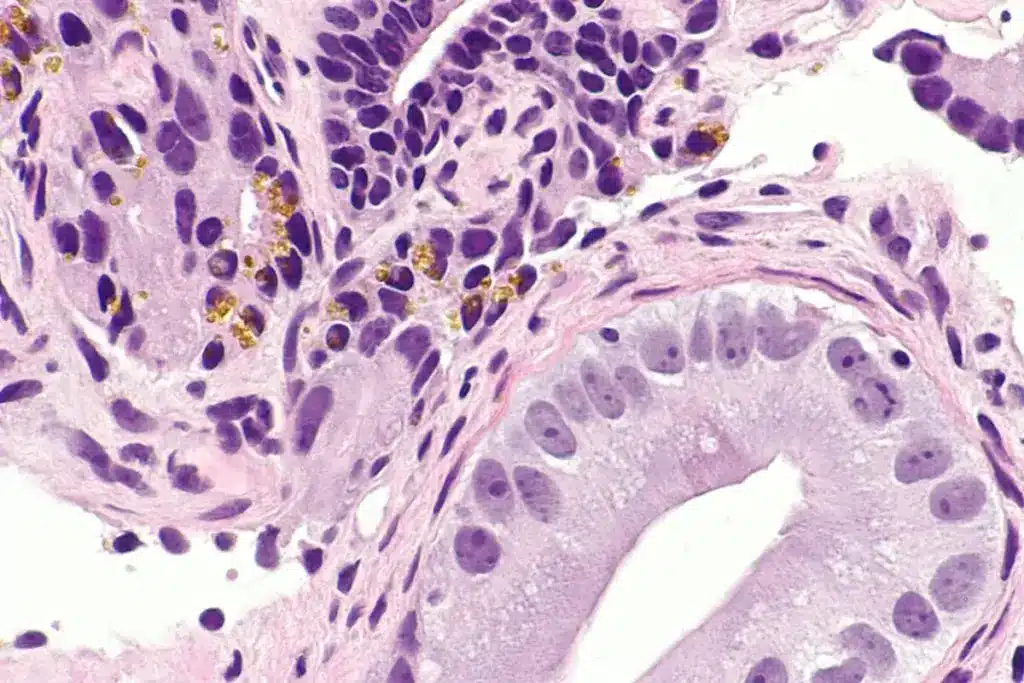

Biopsy and Other Procedures

Even with imaging tests, a biopsy might be needed to confirm bone metastasis. A biopsy takes tissue from the suspected area for a microscope check. It helps find out if the bone lesion is cancer and where it came from.

Other tests, like bone marrow aspiration, might also be done. These tests, along with imaging, help doctors make a precise diagnosis. This leads to a good treatment plan.